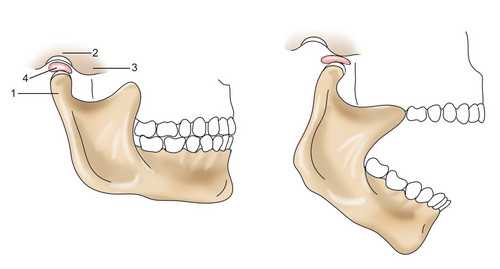

Височно-нижнечелюстной сустав 1 - челюсть, 2 - нижнечелюстные ямки, 3 - бугорок, 4 - внутрисуставной хрящевой диск

Чтобы защитить сустав от перегрузок природа поместила внутрь сустава хрящевой эластичный диск. Диски равномерно распределяют нагрузку на поверхность височно-нижнечелюстных суставов.